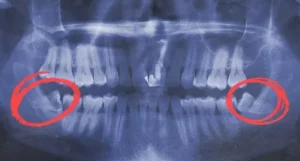

Wisdom teeth removal is a common dental procedure that many people undergo in their late teens or early adulthood. While the surgery is routine, the